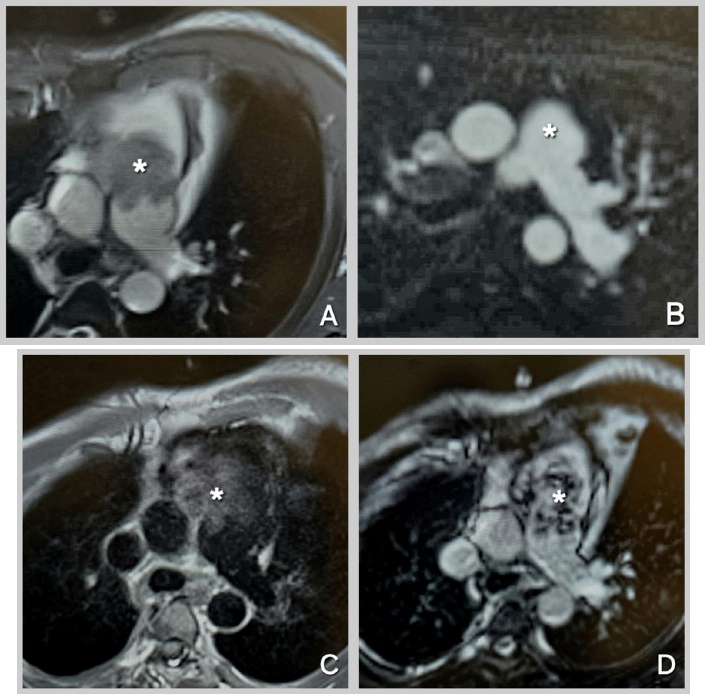

The patient was further investigated with computed tomography (CT), cardiac magnetic resonance imaging (MRI), and positron emission tomography-computed tomography (PET-CT). The CT scan showed a mass extending from the RVOT into the main pulmonary trunk, causing significant stenosis. PET/CT showed a fluorodeoxyglucose (FDG) avid lesion in the right ventricular outflow tract region extending to the right main pulmonary artery and the lobar arteries (Fig. 2A-D). Cardiac MRI showed an enhancing filling defect within the RVOT, main, and right pulmonary arteries, suggestive of a neoplastic process, most probably a pulmonary artery angiosarcoma. Signs of right heart volume and pressure overload were also seen (Fig. 3A-D). The patient also had a right-sided pleural effusion.

Cardiac MRI Sequences for Mass Characterization.

(A): Cine-SSFP (Cine-steady state free precession) sequence at the level of the great vessels, showing an iso-heterogeneous mass in the main pulmonary artery extending from the right ventricular outflow tract (RVOT). (B): Perfusion sequence at the level of the great vessels, demonstrating hyperenhancement of the mass. (C): T1-weighted sequence at the level of the great vessels, revealing an iso-hyper heterogeneous mass in the main pulmonary artery extending from the RVOT. (D): Late Gadolinium Enhancement sequence at the level of the great vessels, showing an iso-hyper heterogeneous mass in the main pulmonary artery extending from the RVOT. Mass indicated by Asterix.